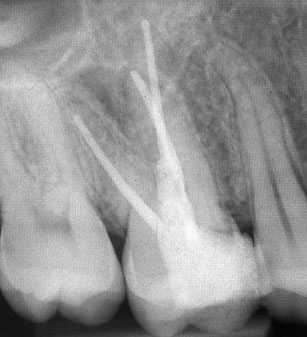

При наличие на огнище на възпаление около корените на зъба добре проведеното лечение води до изчезване на изменението. На снимката долу едва една седмица след пролекуване на каналите се наблюдава известна редукция на патологичния процес. За период от 6 месеца до 2 години е възможно да се наблюдава пълен оздравителен процес.

Винаги е необходимо лекуващият да се стреми към този резултат: